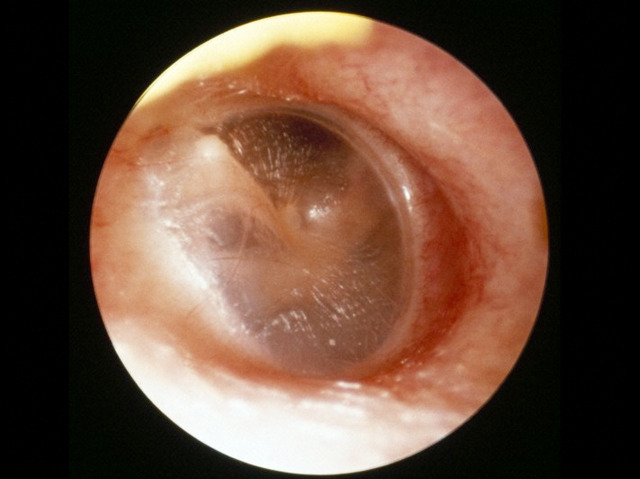

Have you ever experienced that uncomfortable feeling in your ears as an aeroplane takes off? The pressure change as we climb higher into the sky causes unpleasant sensations because our ears have not had time to adjust. Other than deep sea diving, flying is one of the few occasions when we’re aware of our eardrums. Known as the tympanic membrane by scientists, the eardrum separates the middle and inner ear from the environment and converts sound into vibrations that are further processed for our brain to register. Explosions and physical trauma to the ear can cause rupture of the membrane that may lead to infections and hearing difficulty. Some World War II pilots intentionally ruptured their eardrums to stop air pressure problems when flying and the Bajau tribe of the South Pacific do the same to facilitate deep sea diving, albeit often with severe consequences for their hearing.